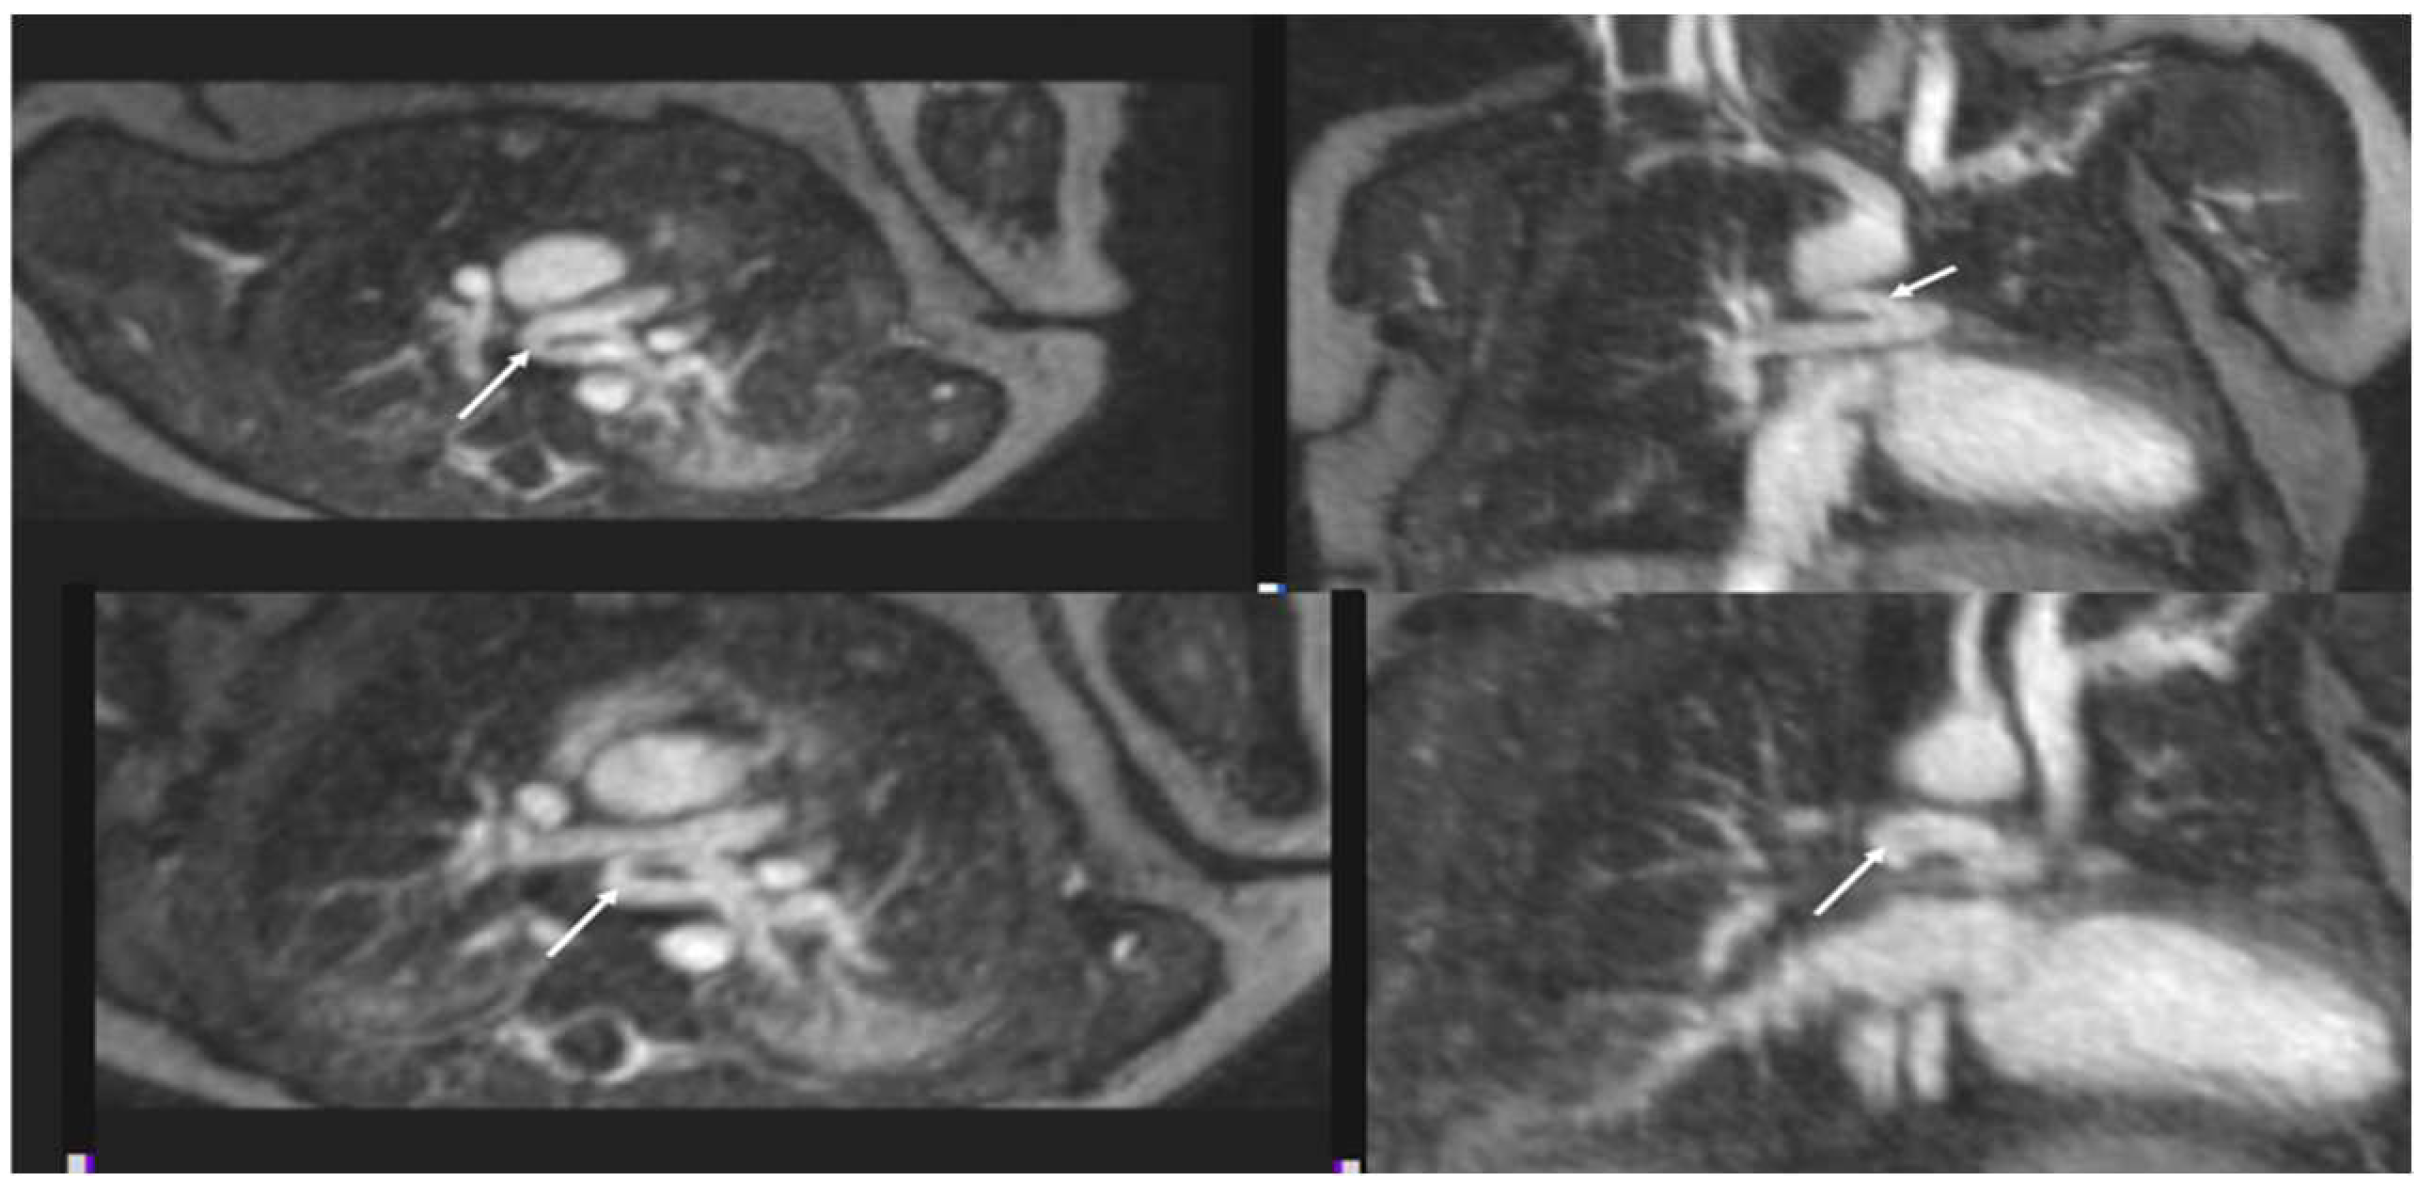

4.1.1. Total Anomalous Pulmonary Venous Connection (TAPVC)

4.1.2. Pulmonary Vein Stenosis